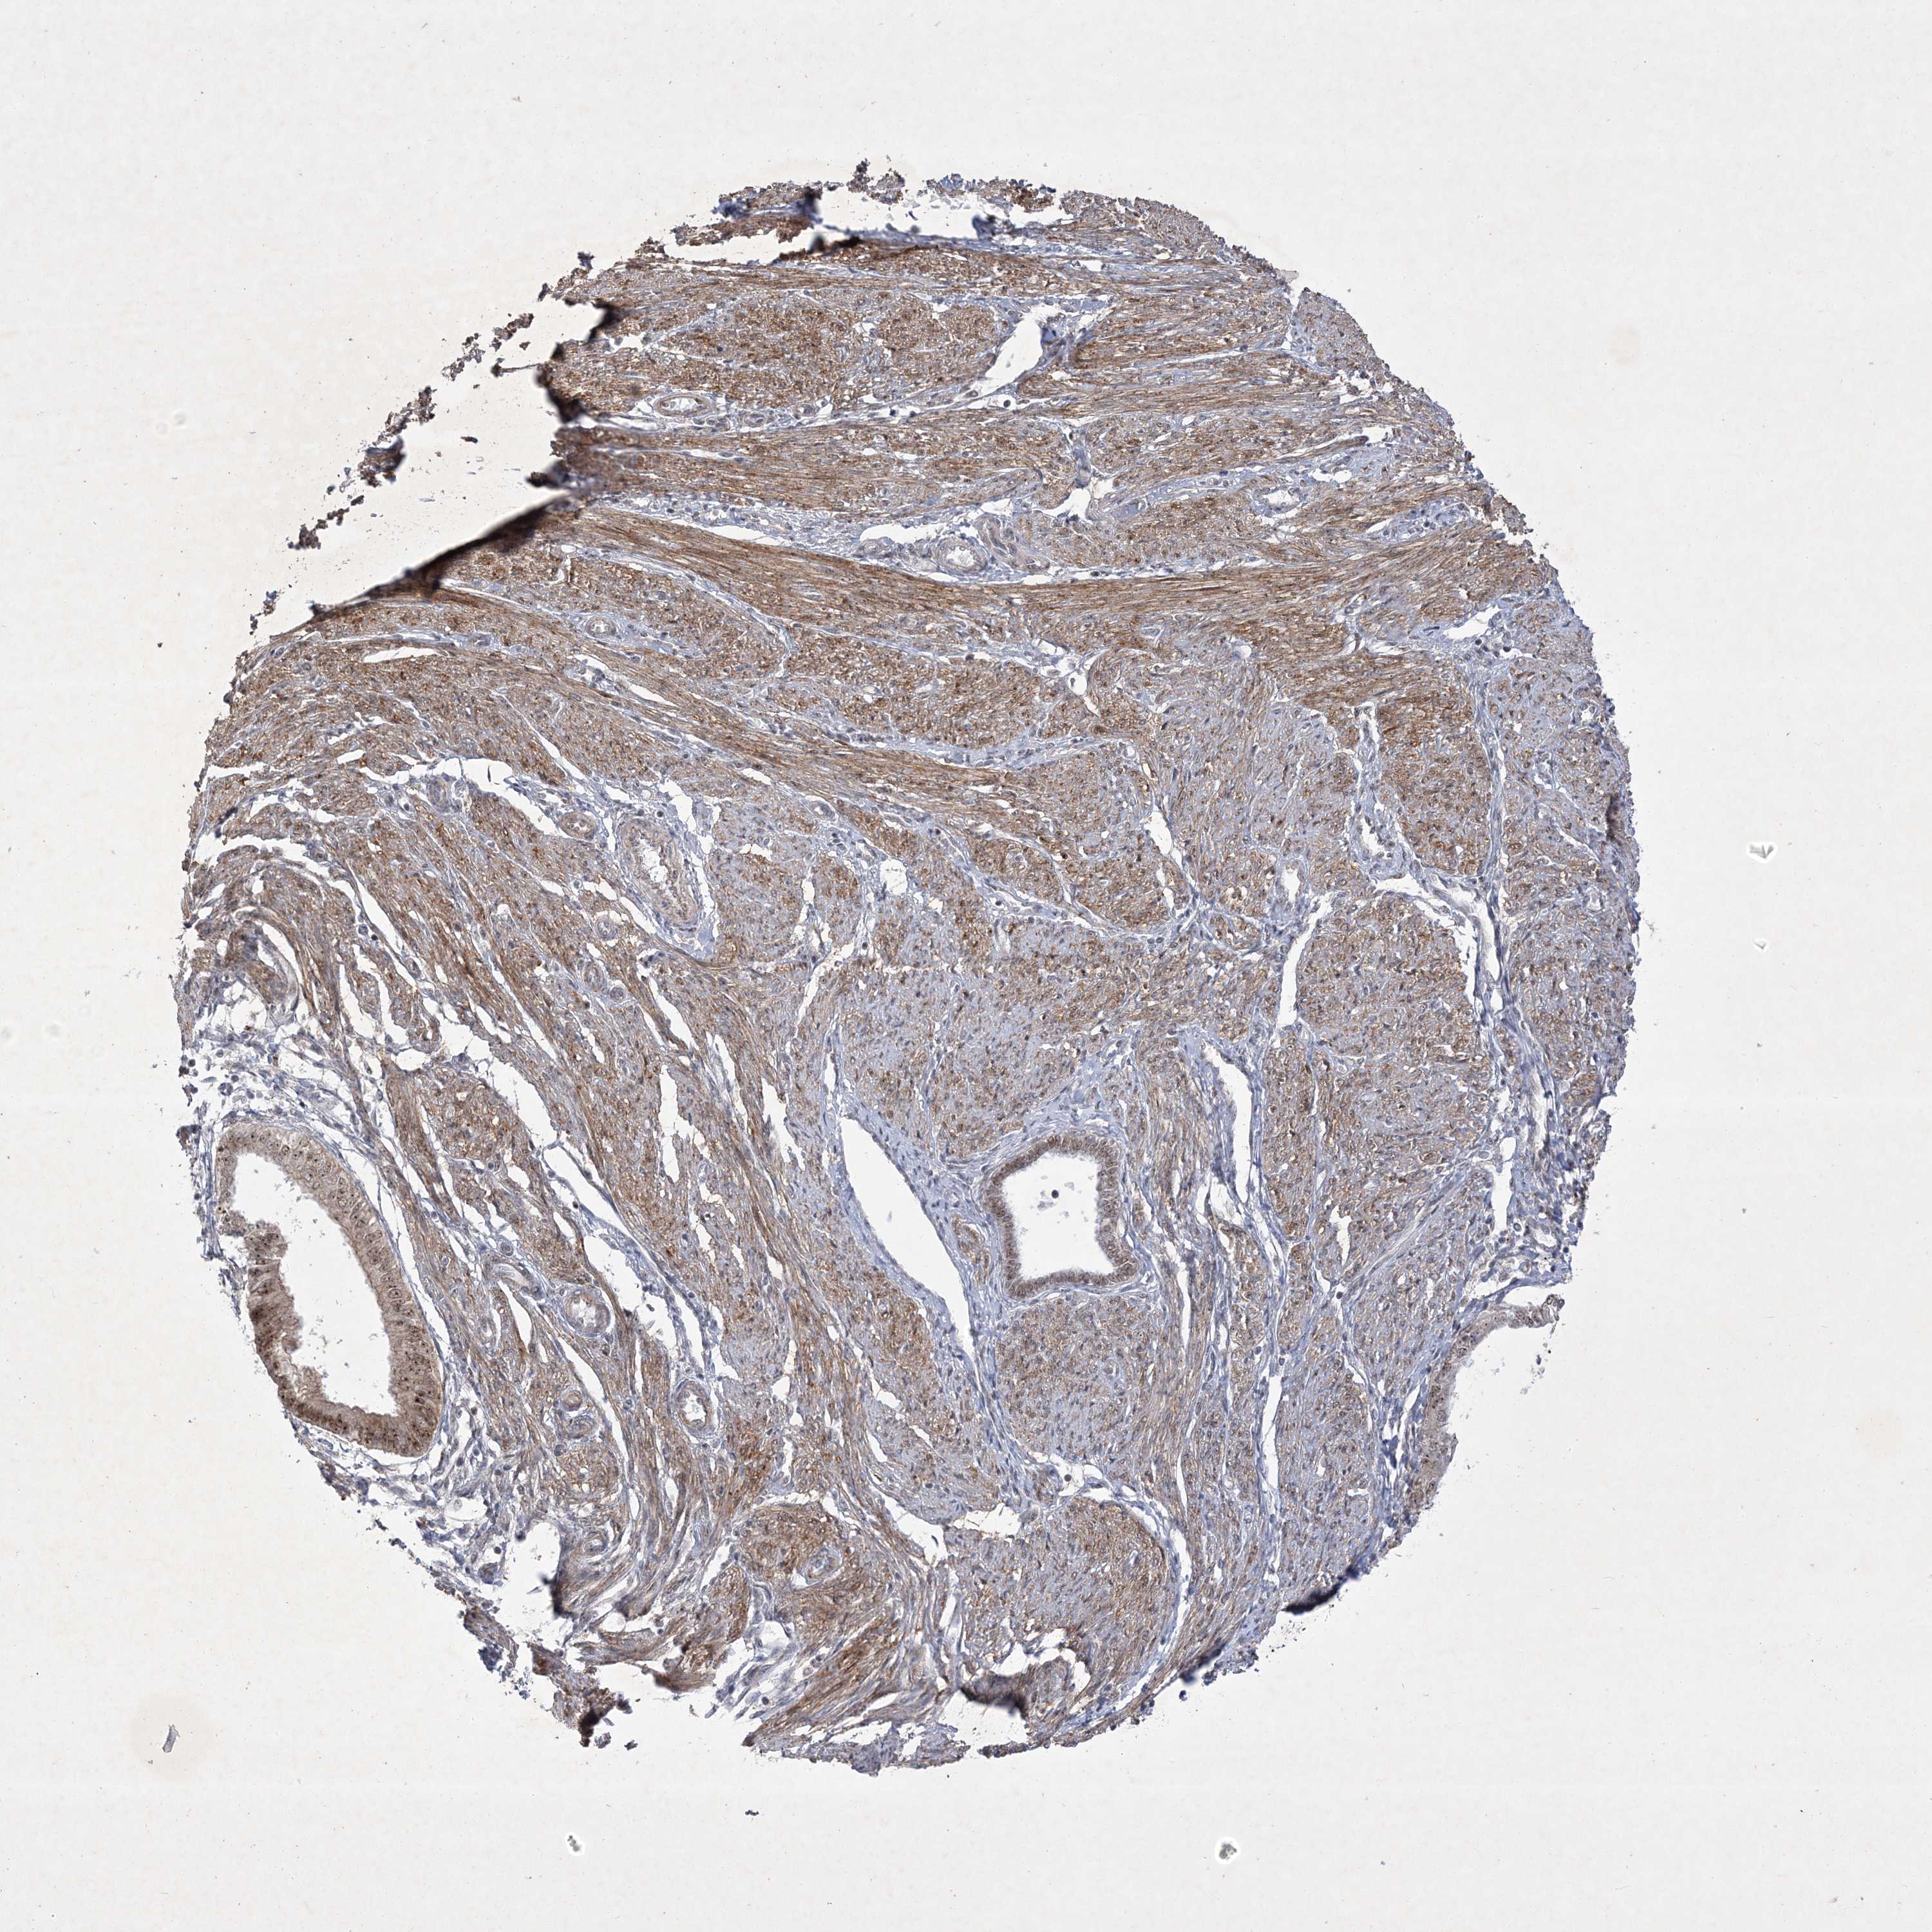

ENDOMETRIAL CANCER - Protein expressioni

A mouse-over function shows sample information and annotation data. Click on an image to view it in a full screen mode. Samples can be filtered based on level of antibody staining by selecting one or several of the following categories: high, medium, low and not detected. The assay and annotation is described here.

Note that samples used for immunohistochemistry by the Human Protein Atlas do not correspond to samples in the TCGA dataset.

Antibody stainingi

Antibody staining in the annotated cell types in the current human tissue is reported as not detected, low, medium, or high, based on conventional immunohistochemistry profiling in selected tissues. This score is based on the combination of the staining intensity and fraction of stained cells.

Each image is clickable and will lead to virtual microscopy that enables deeper exploration of all samples and also displays staining intensity scores, fraction scores and subcellular localization as well as patient and tissue information for each sample.

Antibody HPA036295

Antibody HPA036296

Staining

High

Medium

Low

Not detected

Intensity

Strong

Moderate

Weak

Negative

Quantity

>75%

75%-25%

<25%

None

Location

Nuclear

Cytoplasmic/membranous

Cytoplasmic/membranous,nuclear

Adenocarcinoma, NOS

Adenocarcinoma, metastatic, NOS